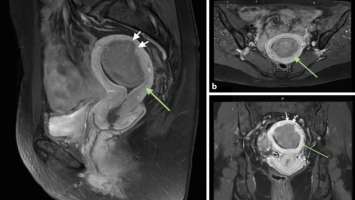

Anhaltende vaginale Blutung zehn Monate nach Re-Sectio

Eine 31-jährige, stillende Patientin stellt sich mit zunehmend übelriechendem Vaginalausfluss und anhaltender Schmierblutung vor. Zehn Monate zuvor hatte sie per Re-Sectio entbunden, bei der es intraoperativ zu einer Uterusatonie kam. Nun zeigt die Vaginalsonographie einen dramatischen Befund, der sofortiges Handeln erfordert.

e.Med Interdisziplinär Icon, Search Icon, Transvaginaler Ultraschall/© Graphicroyalty / stock.adobe.com (Symbolbild mit Fotomodellen), Glaszellentumor der Gebärmutter/© Boeker M et al. / all rights reserved Springer Medizin Verlag GmbH, Extrauteringravidität /© Tsitlakidis I et al. / all rights reserved Springer Medizin Verlag GmbH, Bilaterale ausgedehnte zylindrische Bronchiektasen/© Düsterhöft D et al. / all rights reserved Springer Medizin Verlag GmbH, CT des Uterus einer 47-Jährigen /© Rizos A et al. | all rights reserved Springer Medizin Verlag GmbH, MRT des Beckens: Uterus und Ovarialtumoren/© Hosten AK et al. / all rights reserved Springer Medizin Verlag GmbH, Digitales Blutdruckmessgerät/© Kotchakorn / Stock.adobe.com (Symbolbild mit Fotomodell), Frau tastet ihre Brust ab/© Pheelings Media / Getty Images / iStock (Symbolbild mit Fotomodell), Feten von siamesischen Zwillingen/© Zahn E et al. / all rights reserved Springer Medizin Verlag GmbH, MRT einer intrakavitären Raumforderung/© Lattermann M et al. doi.org/10.1007/s00761-025-01733-0 unter CC-BY 4.0, Aufnahme nach Resektion der Extrauteringravidität/© Antonia Jörger